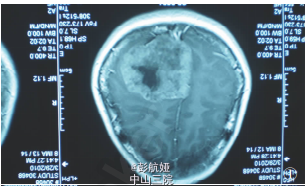

患者女性,37岁。因渐进性头痛2年、右侧头面部及肢体麻木3个月入院。查体:患者意识清晰,双侧视乳头水肿,右侧头面部及肢体感觉减退,右上肢及下肢肌力4-5 级。CT检查,左顶叶见一高密度影肿块,9.5cm*7cm*6.5cm,边缘清楚,中央可见钙化及囊性变(图1),肿块体积巨大,脑中线结构右移(图 2),MRI 显示肿块呈不均匀长T1、长T2信号,GD-DTPA 延迟期有强化效应。CT、MRI 诊断:左顶叶占位,性质待定。临床以左顶叶肿瘤行手术切除治疗,术中见肿块位于中央沟内,与大脑镰相连,大脑镰右移,左顶叶受挤压显著,肿块质硬,活动可,与脑组织无粘连,予肿块完整切除,标本送病理检查。术后患者头面部及肢体感觉恢复,肢体肌力增加,在随访中。